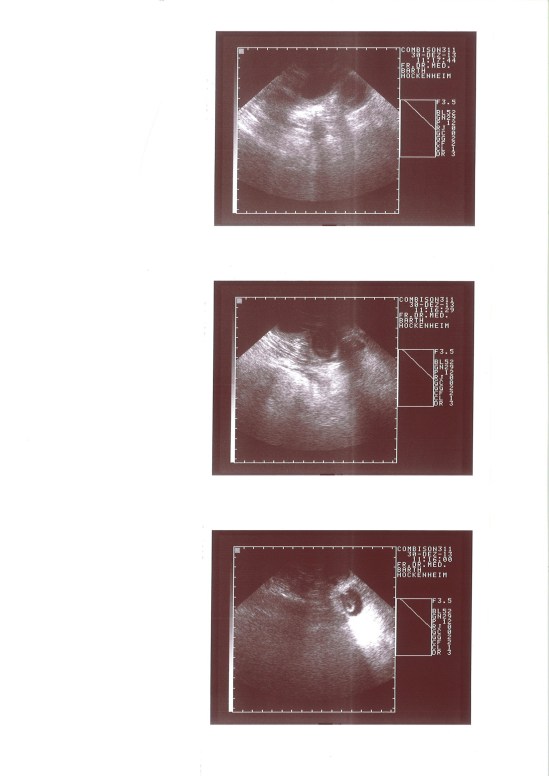

PREGNANCY

20131230114312_00001

pregnancy confirmed !

DAY 35

day 35…..

dakot berry dea 004

day 40…..

dakota 44 day 3 dakota 44 dayday 44…

139

day 47…..

003

day 50…..

012day 53…….